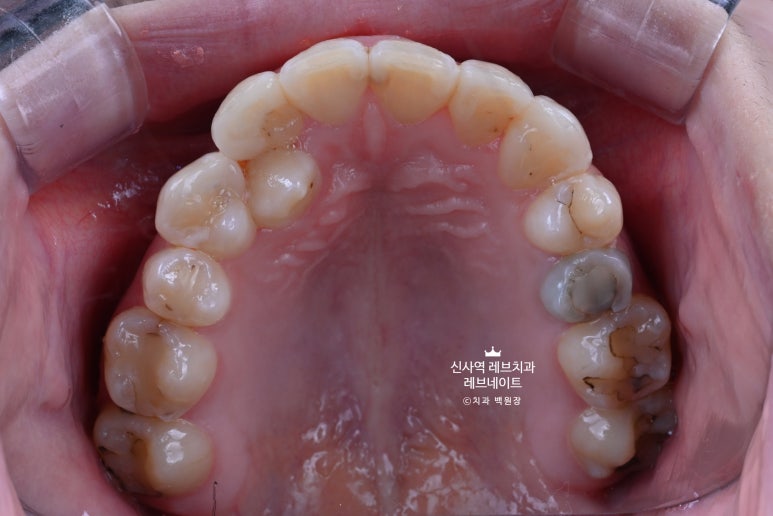

사진을 찍어두고 4개를 신중하게 골라야만 했습니다......

그래도 가운데 앞니는 배열이 고르고, 모양도 괜찮은 편이었기에

위에 표시해 둔 4개의 치아를 모양을 최대한 잡아서 한 번 예쁘게 연출을 해보기로 했습니다.

크라운치료를 하자니, 송곳니가 있어서 송곳니를 무조건 뽑아야 했고...

그래서 중요한 면접이니 최소한으로 다듬기만 하는 최소삭제 라미네이트를 하고, 면접을 잘 보신 뒤에

튀어나온 치아들은 어쩔 수 없이 깎아야만 합니다.

그래야 모양을 가지런하게 만들 수 있지 않겠어요?

그래도 레브네이트로 치료하니까 크라운으로 하는 것보다 치아 삭제를 최소화 할 수 있었습니다.

위에 있는 사진은 치아를 부드럽게 다듬고 나서 모습입니다.

가운데 앞니 두개가 참 따라하기 어렵게 생겼습니다..

모든 작업은 CAD 작업으로 시작됩니다.

치아와 치아 사이의 공간을 재고, 얼마나 치아를 다듬어야 최소인지 측정하고,

또 그걸 바탕으로 라미네이트를 최소한의 두께로 만들고 더 나아가서 무삭제 라미네이트도 가능해지고